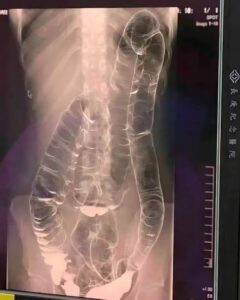

Radiografie unei tinere care suferea de constipație cronică i-a speriat pe medici

Peste două săptămâni făni interne extreme. Imaginile au devenit motiv de îngrijorare reală pentru medici.

În situații de stagnare prelungită a reziduurilor, colonul este forțat să se lărgească pentru a face loc conținutului reținut. În cazul acestei paciente, întinderea severă a pereților intestinali a transformat un organ flexibil într-unul rigidizat și lipsit de ondulațiile obișnuite. Această transformare reduce capacitatea de contracție și întreține cercul vicios al constipației.

Chiar dacă frecvența tranzitului variază de la o persoană la alta, pauze repetate de peste 3 zile fără scaun reprezintă un motiv de atenție medicală. În contextul prezentat, volumul crescut al colonului și absența pliurilor au fost indicii clare pentru o evaluare imagistică și monitorizare de aproape.